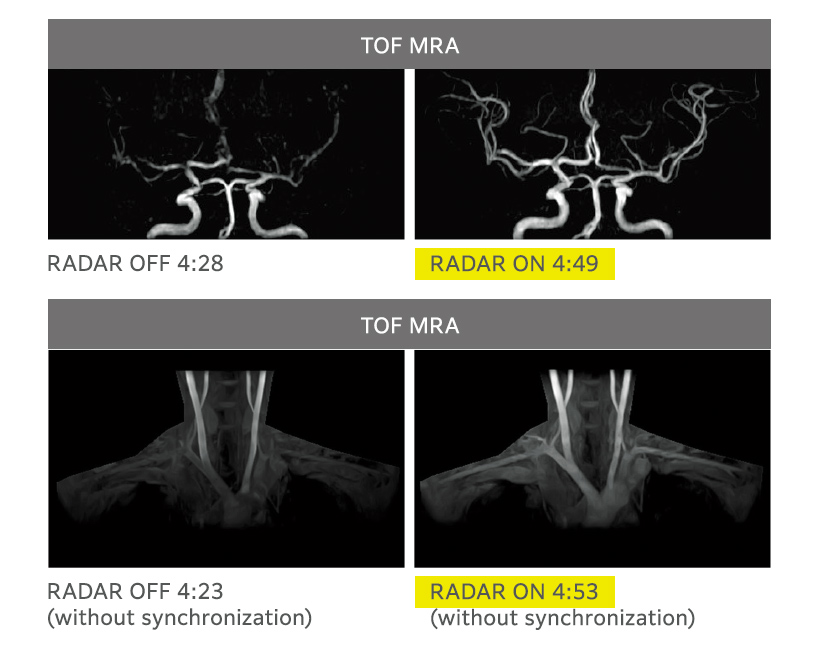

RADAR mitigates motion artifacts enhancing ease of use when imaging with many sequences, all receiver coils, and arbitrary cross-sections. RADAR can be used in combination with highspeed imaging. ECHELON Smart supports TOF and GrE sequences and is compatible with the combined use of RADAR for most of the sequences required for routine head examinations, thus realizing "All Around RADAR."

Effects of RADAR in TOF MRA and GrE T2*WI

RADAR has been applied to GrE sequences using a high-precision signal correction technology. This has enabled the combined use of RADAR in all sequences required for routine head examinations.